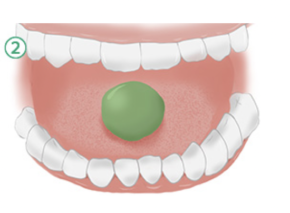

ガムトレーニング

「ガムトレーニング」を1日3分以上続けると舌の機能が回復し、舌に関係する筋肉の力が強くなり舌の位置が正しい位置に戻ってきます

ガムを左右の歯で均等にかむ

片がみを治し、かむ力をつけるため、どちらかがかみにくい場合、かみにくい方でかむ練習をしましょう

ガムをボール状に丸める

舌の動きを良くする為にガムを舌を使って舌の上で丸めます。

舌の中央にガムをのせて上あごの中央に3秒間押しつけて薄く広げる

舌の筋力をつけるために一回で行い円形に広げてください。

舌でガムを上あごに押しつけたままつばを飲みこむ

つばを飲み込んだ後はガムが三角形に伸びるのを確認してください。正しく飲み込めれば舌は芋虫のような動きをして、ガムはのどに向かって三角形に流れます。

①〜④のガムトレーニングを1日3分間以上繰り返しましょう

これが、「できない」場合は、舌の機能が足りません。

まずは他のトレーンニングから始めてみましょう!

舌の機能が足りない例

低位舌で舌の力が正常でない場合、下記の様になってしまいます。「ガムトレーニング」は正しい方法で訓練しなければ舌の機能が回復しません。

かいり歯科クリニックでは虫歯予防になるキシリトール100%のトレーニングふうせんガムを使用して舌のトレーニングである『ガムトレーニング』のアドバイスをしております。